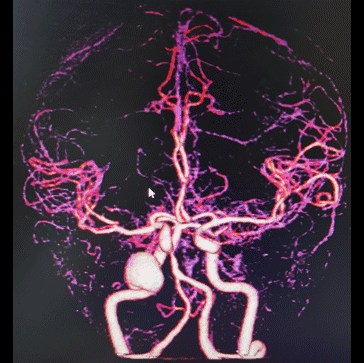

图2 头颅CTA提示右颈内末端动脉瘤,前交通动脉瘤

右颈内动脉交通段以远瘤样扩张,钙化明显,载瘤动脉完全瘤化,局部可见多处小阜突起,无明显瘤颈,最大约16mm╳11mm,前交通囊状动脉瘤约4mm╳3mm,瘤颈约4mm。